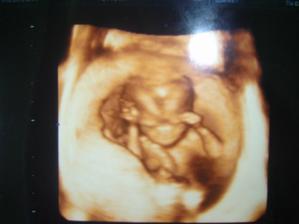

1/12/08: byli jsme na 3D ultrazvuku, miminko už nebylo tak klidné jako na předchozích UTZ, nedalo se pomalu ani zachytit, ale bude to prý z 95% holčička, máme radost!!!!!!!!! Je to pěkná čahounka (asi po mně🙂)), měří 20cm, váží 215g.